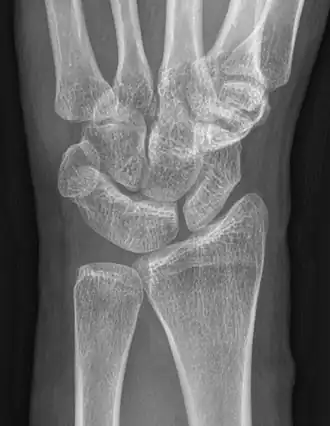

An example of a coalition between the trapezoid and capitate carpal bones

The lunate and triquetral bones are the most common carpal bones to fuse together, resulting in a lunotriquetral coalition in 1% of people. 60% of patients with a lunotriquetral coalition will have it bilaterally.[1] Among isolated incidents the capitate and hamate bones are the next most common to fuse followed by the pisiform-triquetrum, trapezium-trapezoid, scaphoid-capitate, and triquetrum-hamate.[3]